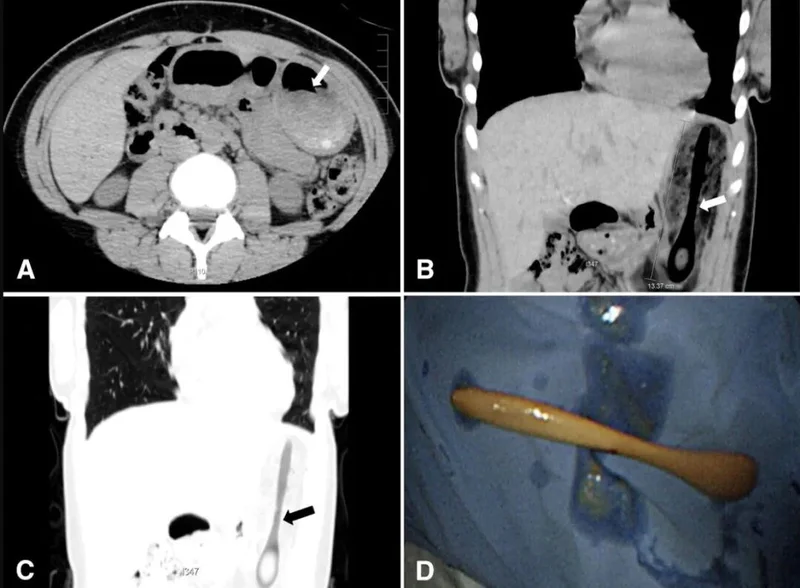

(CT可以清晰看到勺子)

(CT片和木勺)

据她形容,这把木勺大约手掌长,也就是大概15~20厘米,而且勺柄肉眼可见地要比Amelinckx那把金属勺更粗。

不过A就没有Amelinckx那么心大了,她立刻去了急诊。医生们看着CT都想不通了,问她:“你到底是怎么吞下这么大的东西的?”